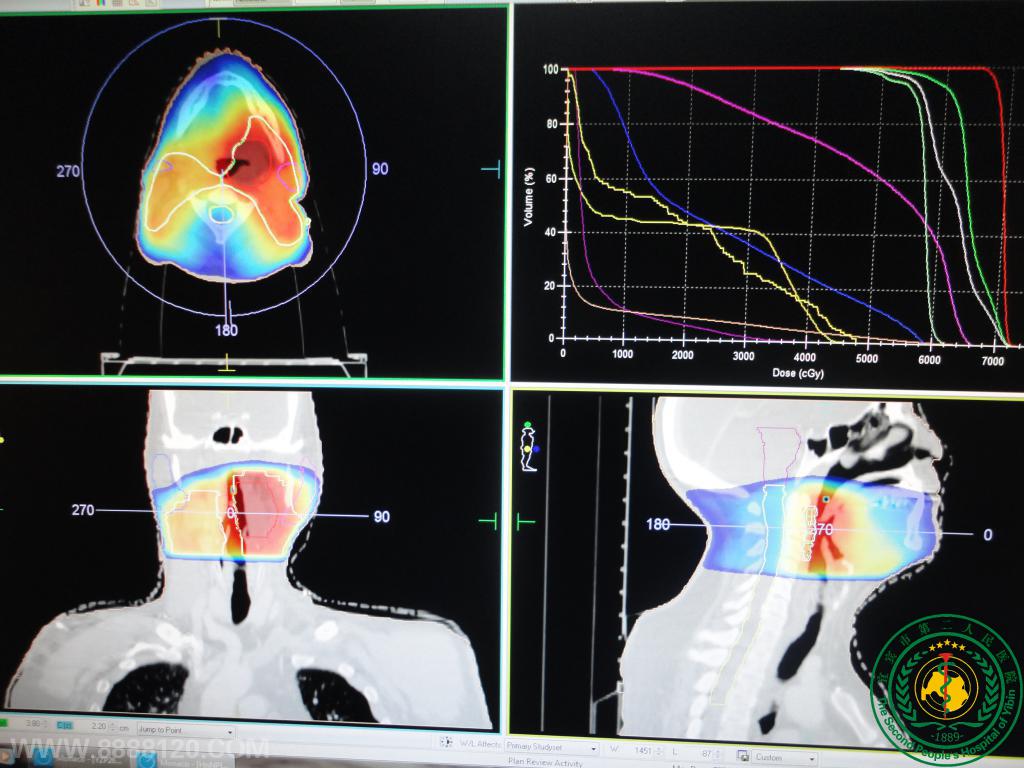

盆腔宫颈癌及头颈下咽癌、喉癌VMAT调强靶区高剂量、正常组织低剂量及剂量验证高度吻合